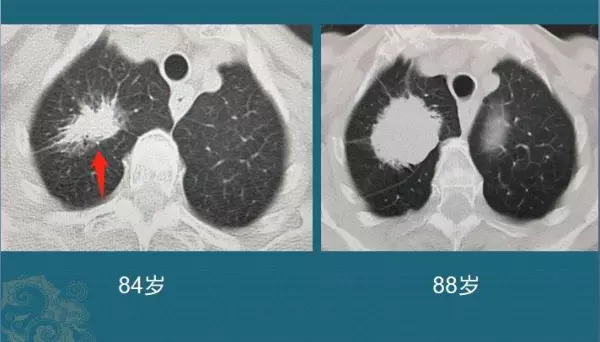

这位老人84岁,因为咳嗽、胸闷查出混合磨玻璃结节,形态不规则,边缘有清晰的磨玻璃影,同时伴有胸膜牵拉,是典型肺腺癌的特点。

但她比较幸运,癌细胞增殖速度不快,今年已经88了,精神头还不错!